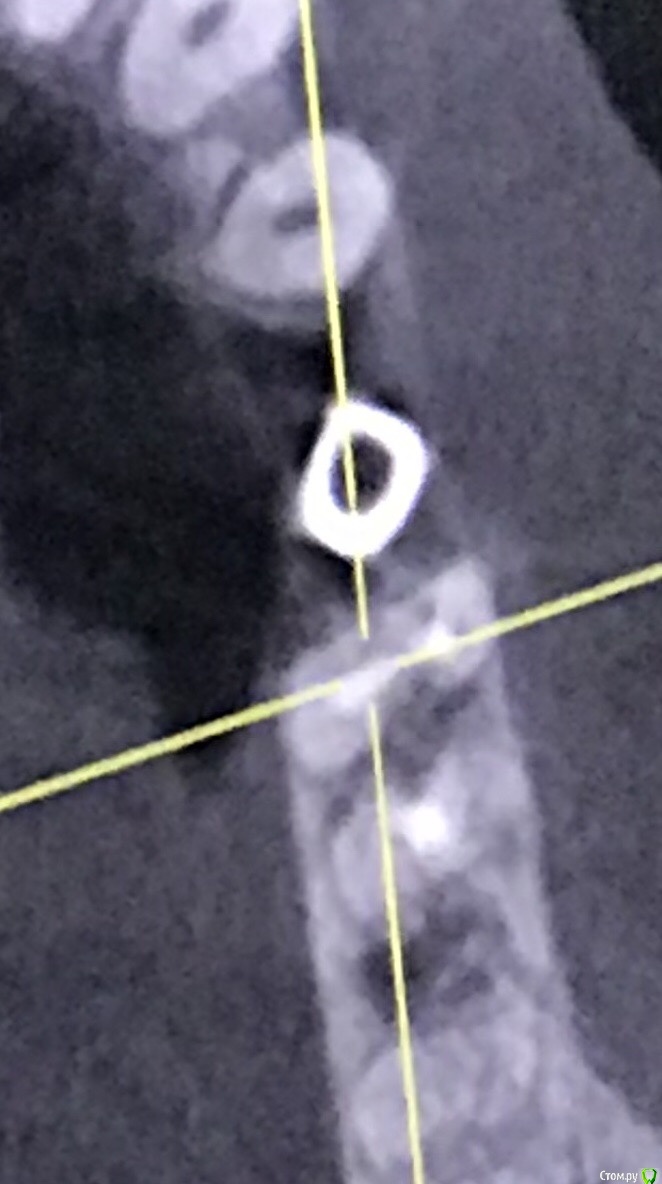

111 Опубликовано 26 декабря, 2020 Автор Поделиться Опубликовано 26 декабря, 2020 (изменено) Iroil, спасибо большое за ответ.46 был кариес но не болел, периодонтита не было, никаких воспалений на верхушках не было. То есть 46 просто пролечили - обработали каналы, заложили кальций, и тд. Делалось под микроскопом, доктор очень хороший. По поводу 45 - изначально кости было достаточно по высоте, по объему пришлось подсыпать gen-oss 0,5 в момент имплантации, плюс сст с бугра. Вообще всё было хорошо, особо сильно не болело, без отёка зажило. В момент снятия швов - обнаружилась убыль кости в области 46, слегка оголился корень ближайший к 45, но мы как-то это не обсуждали с доктором. Установили Фдм, все ок.И вот пришло время ортопедии - это было летом 2019 - ортопед не захотел работать с имплантом, у которого на снимке оголена шейка. Десны достаточно при этом. Имплант не запротезирован.Спустя пару дней на визите у хирурга - я прошу выкрутить 45, мне отказывают, принято решение либо оставить как есть, либо подсыпать кости немного.Сейчас, декабрь 2020, я хожу с фдм и уже точно понимаю, что надо переустановить 45, но хирург предлагает 2 варианта:- оставить как есть и делать ортопедию (т.к. десна хорошая);- удалить 45 и 46 для создания удобного рабочего поля и имплантация 45, 46.Вот я пытаюсь понять, нельзя ли просто 45 выкрутить? Аккуратно удалить 45 не получится? (Очень не хочется расставаться с 46, сам по себе он не болит при накусывании и постукивании). Изменено 26 декабря, 2020 пользователем 111 Ссылка на комментарий

Irouil Опубликовано 26 декабря, 2020 Поделиться Опубликовано 26 декабря, 2020 Имплант запротезирован? Когда был установлен? Маловероятно, что описываемые жалобы связаны с имплантатом. Скорее причина в зубе - решение о его лечении лучше спросить в терапевтическом разделе, хирурги зубы не лечат. Если имплантат не запротезирован, то мне кажется логичнее его удалить - очень комрромиссно придется протезировать. Если уже есть коронка - нужен рентген с ней. 1 Ссылка на комментарий